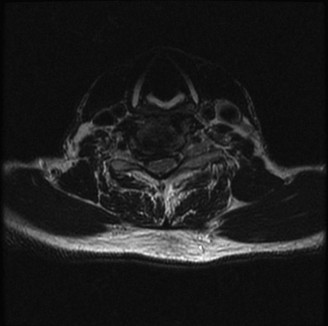

Initial trauma radiographs demonstrated a loss of anterior and middle column height at L1, with a focal kyphotic deformity. However, plain films are vastly insufficient for definitive surgical planning in thoracolumbar trauma. A high-resolution, fine-cut Computed Tomography (CT) scan of the entire spine was obtained. The CT images confirmed an L1 burst fracture with severe comminution of the vertebral body. Sagittal and axial reconstructions revealed 50% canal compromise secondary to a large retropulsed bone fragment originating from the posterosuperior aspect of the L1 vertebral body. Furthermore, the CT demonstrated 25 degrees of segmental kyphosis measured from the superior endplate of T12 to the inferior endplate of L1.

A critical finding on the axial CT slices was a vertical, split fracture propagating through the L1 lamina. This is a highly significant morphological feature. A lamina fracture in the setting of a burst fracture with retropulsion strongly correlates with a dural tear and potential entrapment of the cauda equina nerve roots. When the vertebral body bursts posteriorly, the pedicles are driven outward, and the lamina fractures as the spinal canal attempts to expand to accommodate the retropulsed bone. If the dura is lacerated, nerve roots can herniate through the dural defect and become incarcerated in the laminar fracture site.

Magnetic Resonance Imaging and the Posterior Ligamentous Complex

The MRI, particularly the Short Tau Inversion Recovery (STIR) and T2-weighted sagittal sequences, provided the definitive diagnosis. The images demonstrated profound hyperintensity and discontinuity of the ligamentum flavum, the interspinous ligaments, and the supraspinous ligaments at the T12-L1 level. The facet joint capsules were also disrupted, indicated by fluid within the joints. This complete failure of the PLC means the posterior tension band is gone. Regardless of the bony parameters, this spine cannot resist physiological flexion loads. If treated non-operatively, this injury will inevitably lead to progressive kyphosis, delayed neurological deficit, and intractable pain.